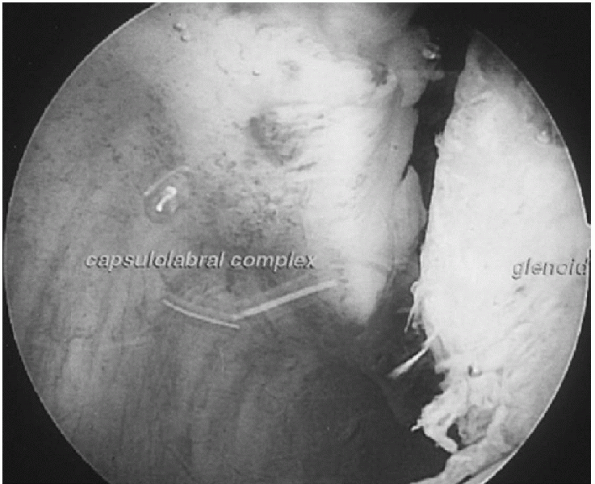

![]() |

Figure 17-2 Arthroscopic view of a Bankart lesion, left shoulder, sitting position viewed from posteriorly.

instability has been studied extensively. The detachment of the labrum

from the anterior-inferior glenoid is the essential lesion leading to

anterior instability. By displacing the anterior labrum, glenoid depth

is decreased by up to 50% and

passive restraints, such as the concavity-compression mechanism discussed earlier, are also lost.